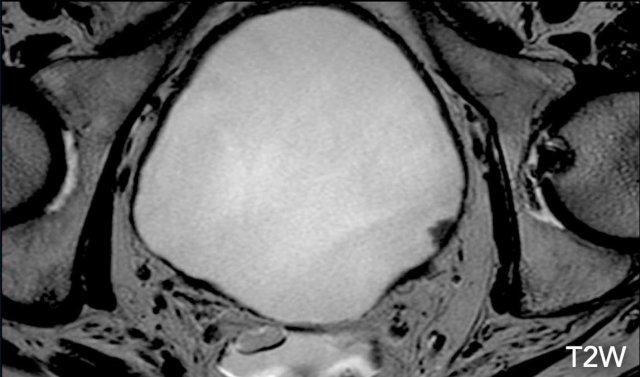

VI-RADS 3

- T2W Điểm 3: Vắng mặt cuống trong u nhú hoặc vắng mặt lớp trong dày lên tăng tín hiệu trong u dạng phẳng, trong khi vẫn duy trì đường giảm tín hiệu liên tục của cơ thành bàng quang (muscularis propria).

- DCE 3: Không có các dấu hiệu của phân loại 2 trong khi vẫn duy trì đường giảm tín hiệu liên tục của cơ thành bàng quang.

- DWI 2: Không có các dấu hiệu của phân loại 2 trong khi vẫn duy trì đường giảm tín hiệu liên tục của cơ thành bàng quang.

Trước tiên hãy quan sát các hình ảnh.

Bạn nhận thấy những dấu hiệu gì?

Hình ảnh

Có một khối u dạng phẳng ở thành bàng quang bên trái.

Do không có cuống khối u và lớp trong, nhưng cũng không có sự gián đoạn rõ ràng của lớp cơ, trường hợp này nên được chấm điểm T2W: 3.

Tiếp tục…

Bước tiếp theo là đánh giá các hình ảnh DCE và khuếch tán để phân biệt giữa VI-RADS 2, 3 và 4.

Tiếp tục xem các hình ảnh DCE và khuếch tán…

Trên chuỗi xung DCE, không có các dấu hiệu của phân loại 2 trong khi vẫn duy trì đường giảm tín hiệu liên tục của cơ thành bàng quang.

Ngoài ra, trên chuỗi xung DWI cũng không có sự gián đoạn rõ ràng của lớp cơ.

Điểm VI-RADS cuối cùng: 3